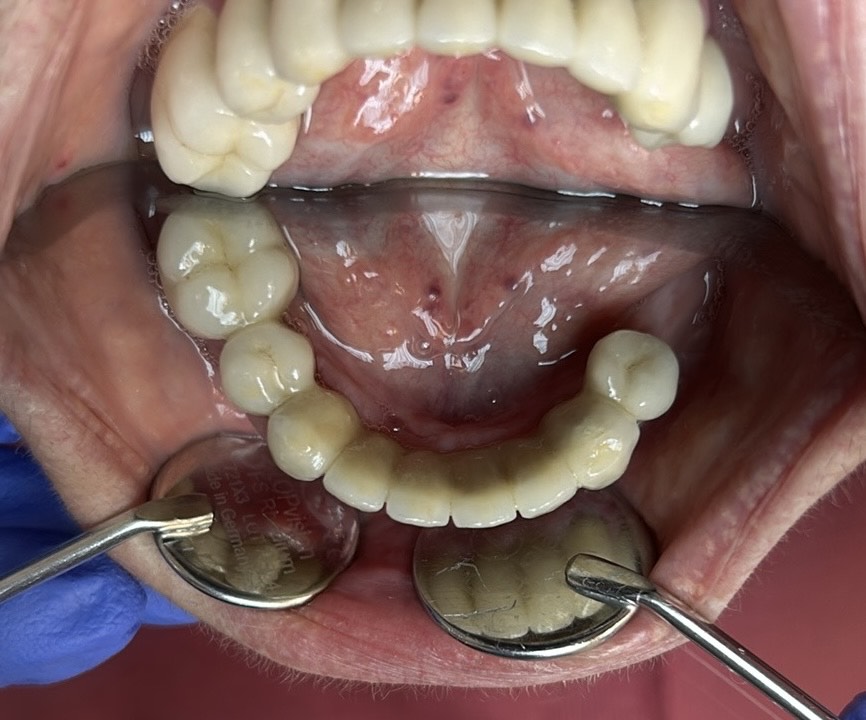

Előtte-utána: Régi alsó fémkerámia körhíd cseréje